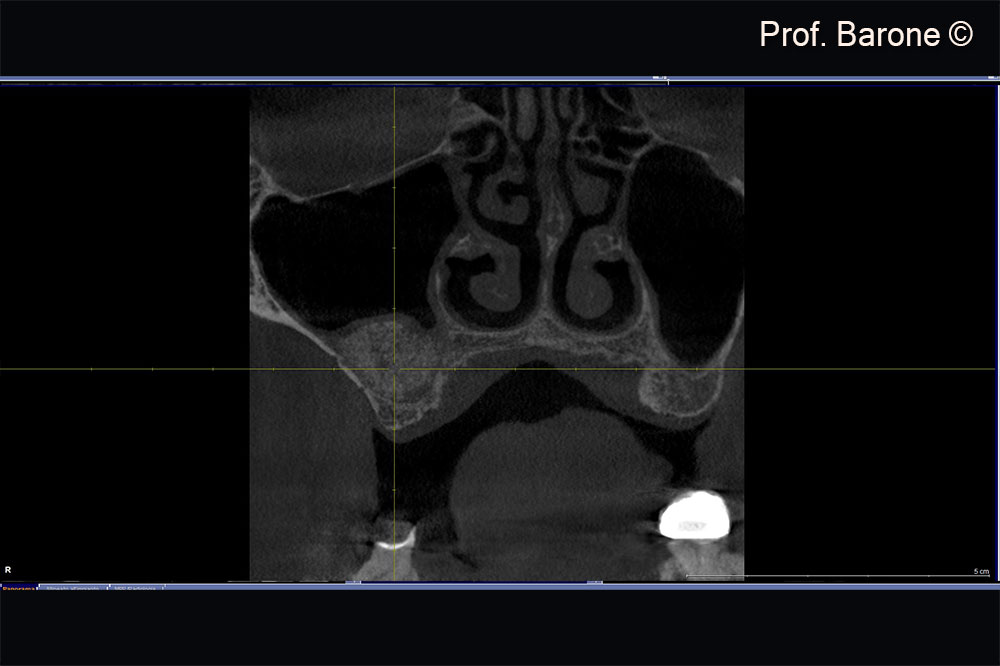

Residual ridge height doesn’t allow implant placement

Residual ridge height doesn’t allow implant placement, sinus membrane hypertrophy

X-Ray examination 7 months after Sinus Lift